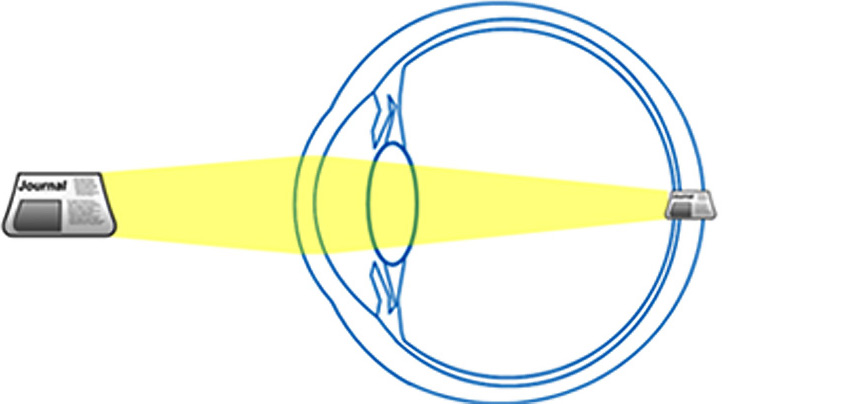

En augmentant sa puissance, le cristallin permet de corriger cela en ramenant l'image de l'objet sur la rétine.